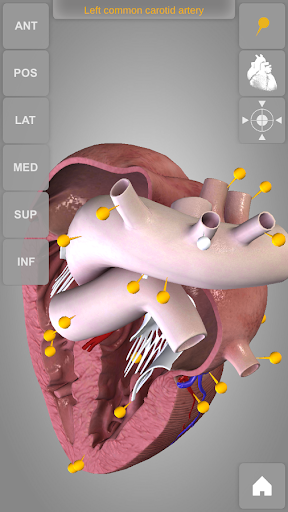

The human heart anatomical 3D model is revolvable in any direction giving a 360° view of the object.

User can choose external view or section view. Moreover, the names of specific anatomical areas can be shown touching the related pins (available in the full version only).